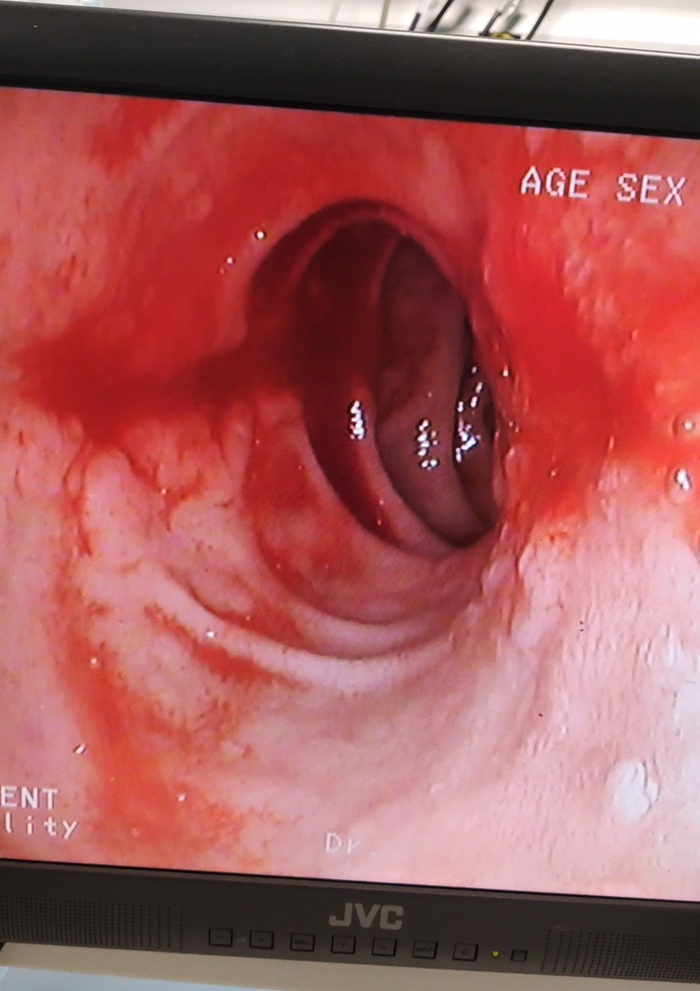

Через водительскую дверь, задние заблокированы, залезаю назад, Палыч даёт катетер и светит фонарем, чуть откидываю Татьяну и мою шею. Пожалуй самая экзотичная постановка внутренней Яремы ( внутренней яремной вены). Самый ближний доступ, из всех доступных самый близкий к верхушке легкого, более подходящий для пункции, но из дальнего в условиях гоповолемии и сидячего положения я ее просто не поймаю и это точно не подклюк.

Значит аллергии на новокаин нет, погнали. Как же все таки не удобно: ножки sternocleidomastoideus, удар 45 градусов, направление на сосок 1,5-3 см. Одышка не делает лучше, но иначе она не может. Отлично. Контроль крови в шприце.

- Давай 8-8,5, меньше эндоскоп не пройдёт.